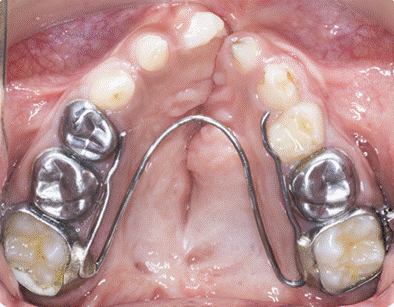

A W-arch palatal expansion appliance was fabricated and cemented. It was activated and monitored for nine months to achieve an adequate transverse maxillary width and dental arch form for subsequent alveolar bone grafting (Figure 5).

Figure 5. W-arch Palatal Expansion Appliance Cemented for Transverse Maxillary Arch Form Preparation Before Alveolar Bone Grafting

Activation began in April with initial mesial contact of 25 mm and distal contact of 39 mm. The patient underwent regular orthodontic follow-up during this period. Subsequent observations and expansions were recorded in May, July, and October. In November, the appliance was maintained without further expansion. Finally, the appliance was removed in February 2025 in preparation for the surgical procedure. Throughout the treatment, activation protocols, retention periods, and appliance adjustments were documented during regular visits. The expansion aimed to correct bilateral posterior crossbite and create sufficient interdental space in the canine-to-canine region, facilitating graft placement and orthodontic tooth movement.

Expansion progress and transverse changes were monitored clinically and radiographically. The appliance successfully achieved the intended widening of the maxillary arch, correction of posterior crossbites, and creation of space in the alveolar cleft region to facilitate future grafting.